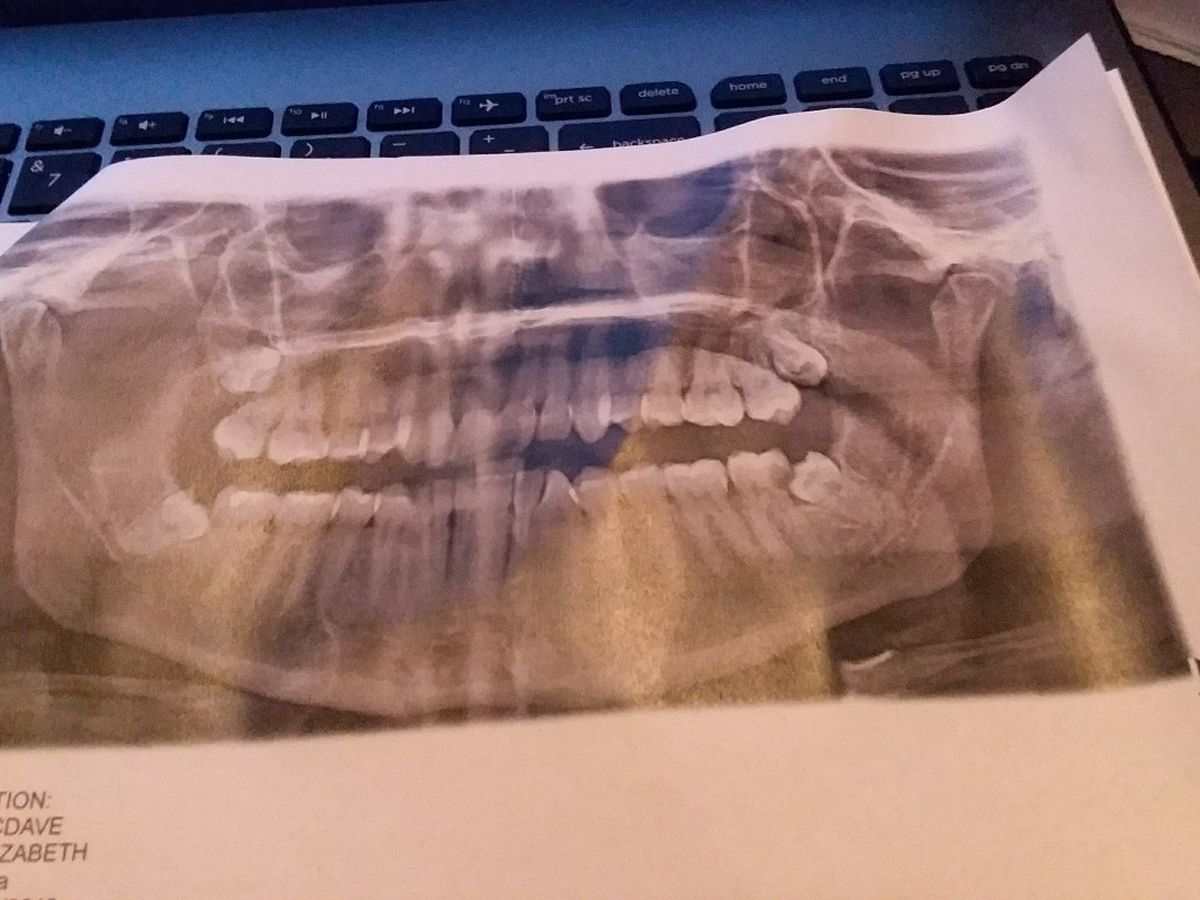

Hello, my name is Elizabeth, I'm 30 years old and I live in southern AZ. I've been having these wisdom teeth pains for the past several years and have recently lost my medical/dental insurance and haven't had a chance to sign up again. I've finally got lucky and found a dentist that did a free x-ray to see how bad my teeth were and after some discussions, I would need to have 1,000$ as a down payment and then pay off the remaining balance over the next 6+ months.